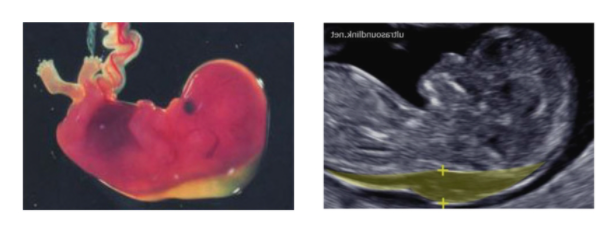

Nuchal Translucency [NT] Scan